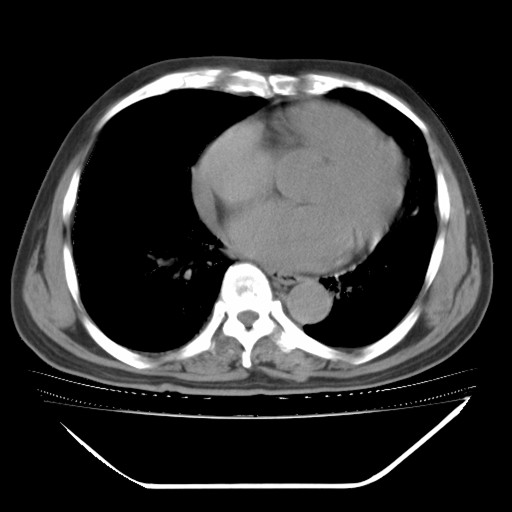

以下是引用hhcckk在2009-5-29 10:34:00的发言:[br]左下肺片絮状边缘模糊影,考虑感染,建议治疗后复查[br]